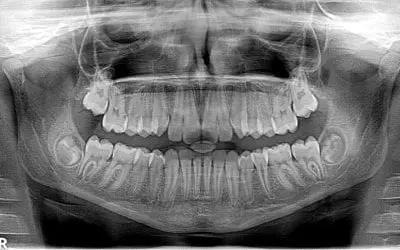

Why Does the Dentist Number my Teeth?

You may have heard your dentist dictating numbers to the dental assistant while examining your teeth. They may say something like this: “Cavity in 4-3, missing 1-8.” With references like these, your dentist is telling...